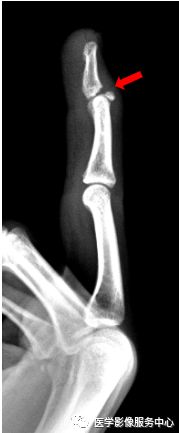

右手拇指近节远端见斜行骨折透亮线,断端稍分离移位,右手拇指近节远端骨折。

右手中指远节近端背侧关节处见游离骨片影。右手中指远节骨折